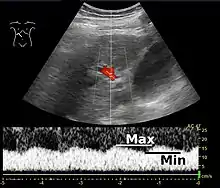

Doppler ultrasonography of the portal vein over 5 seconds, showing peaks of maximal velocity, as well as points of minimal velocity.

Ultrasound is routinely used in the evaluation of cirrhosis. It may show a small and nodular liver in advanced cirrhosis along with increased echogenicity with irregular appearing areas. Other liver findings suggestive of cirrhosis in imaging are an enlarged caudate lobe, widening of the fissures and enlargement of the spleen. An enlarged spleen (splenomegaly), which normally measures less than 11–12 cm in adults, can be seen and may suggest underlying portal hypertension. Ultrasound may also screen for hepatocellular carcinoma, portal hypertension, and Budd-Chiari syndrome (by assessing flow in the hepatic vein). An increased portal vein pulsatility is an indicator of cirrhosis, but may also be caused by an increased right atrial pressure.[33] Portal vein pulsatility can be quantified by pulsatility indices (PI), where an index above a certain cutoff indicates pathology:

Pulsatility indices (PI)

IndexCalculationCutoff

Average-based(Max – Min) / Average[33]0.5[33]

Max-relative(Max – Min) / Max[34]0.5[34][35]–0.54[35]